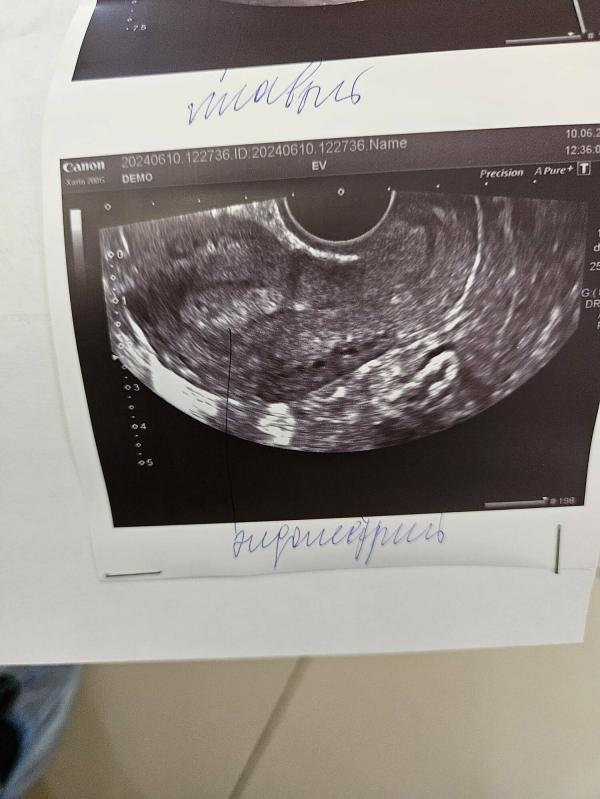

Сегодня сходила на узи, врач сказал что вроде что-то и да и нет, не знаю что и думать..Отправил сдать кровь на ХГЧ, сказал если по анализам крови покажет 5-6 недель, то это скорее всего внематочная.

@mommy.37 ну он сказал что если по узи покажет 5-6 недель то значит где-то не там он закрепился